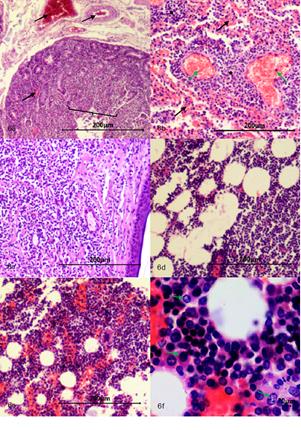

Intestino delgado. Se evidencia severos cambios microcirculatorios, múltiples focos de congestión, hemorragia y enlodamiento con distribución multifocal en mucosa, submucosa, muscular. La luz con gran cantidad de detritos celulares, se evidencia focos con modera atrofia y fusión de las vellosidades, focos con cambios asociados a muerte celular en la punta de la vellosidad y escasos focos de hiperplasia del epitelio que recubre la mucosa, núcleos con picnosis, cariorrexis y cariolisis, moderado infiltrado inflamatorio linfoplasmocitario con distribución difusa, severo edema de la submucosa (Figura 6a).

Fuente: Área de cátedra y servicio de patología veterinaria de la Universidad de Nariño.

Figura 6 (a) Intestino delgado 4x con cambios microcirculatorios, múltiples focos de congestión, hemorragia y enlodamiento con distribución multifocal en mucosa y submucosa (flechas negras), mucosa con atrofia y fusión de las vellosidades (llave). (b) Pulmón 10x con severos cambios microcirculatorios (múltiples focos de congestión (flechas verdes), hemorragia y enlodamiento (flechas negras) con distribución multifocal, presencia de múltiples focos correspondientes a células neoplásicas de origen linfoide las cuales corresponden a metástasis pulmonar (estrellas negras). (c) Piel 4x, dermis con evidencia de proliferación celular neoplásica de origen linfoide, se organiza a manera de paquetes celulares densos pobremente delimitados por estroma de tejido conectivo con un patrón de distribución infiltrativo. (d) Tejido adiposo 10x con presencia de células neoplásicas de origen linfoide. (e) Médula ósea 10x, (f) Médula ósea 40x, se evidencia aumento de la fracción celular con presencia de células neoplásicas de origen linfoide (flechas verdes).

Pulmones. Severos cambios microcirculatorios y múltiples y extensas áreas de congestión, hemorragia, enlodamiento y edema con distribución difusa, presencia de múltiples focos correspondientes a células neoplásicas de origen linfoide; adicionalmente en epitelio bronquiolar se evidencian focos con cambios asociados a muerte celular, áreas de moderada hiperplasia del mismo, moderada hiperplasia de células caliciformes, focos de aplanamiento del epitelio bronquiolar y severo infiltrado inflamatorio predominantemente mononuclear compuesto por macrófagos, células plasmáticas y escasos PMNs neutrófilos con distribución bronquiointersticial (Figura 6b).

Piel. Epidermis aparentemente normal, en la dermis se evidencia proliferación celular neoplásica de células origen linfoide la cual se organiza a manera de paquetes celulares densos y en algunos áreas se organizan en forma de cordones pobremente delimitados por estroma de tejido conectivo que compromete a dermis superficial, dermis profunda, y tejido subcutáneo y tejido muscular. Las células son de forma redondeada núcleos grandes muy escaso citoplasma con moderado pleomorfismo celular, moderada anisocitosis, y moderada megalocitosis. Se evidencia moderado pleomorfismo nuclear, moderada anisocariosis y severa megalocariosis. No se contabilizaron figuras mitóticas en diez campos al azar a 400X, adicionalmente se evidenció la presencia de células neoplásicas dentro de lumen de algunos vasos sanguíneos (Figura 6c).

Tejido adiposo. Presencia de extensas áreas correspondientes a proliferación de células neoplásicas de origen linfoide con características similares a las mencionadas en hígado y páncreas (Figura 6d).

Médula ósea. Se evidencia severo aumento de la fracción celular con presencia múltiples focos de células neoplásicas aparentemente de origen linfoide (Figuras 6e, 6f).